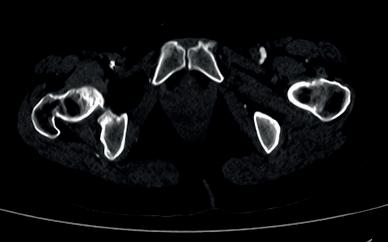

Left: Pre- and postoperative images (courtesy of Dittmar Böckler) of the first European implantation of the Gore Tag TBE; above: Dittmar Böckler performing the implantation